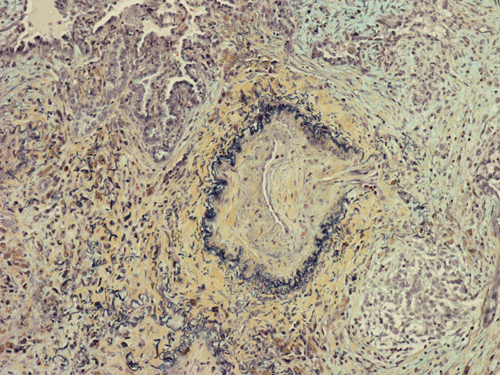

At scanning magnification (Panel A), the lung parenchyma is replaced by some coalescing fibrous nodules. The degree of involvement is variable at different fragments (Panel B and C). In the less affected areas, there are some fibrotic thickening of the septa (Panel C). In some areas, the changes are minimal and the pleural appear to be uninvolved (Panel D and E). In low to medium magnifications, these nodules of fibrosis contains a large number of hemosiderin laden macrophages (Panel F and G) admixed with fibrous tissue. The diagnostic tissue, however, is present in areas with increased cellularity. In these areas, there is a background of cells with a moderate amount of cytoplasm and bland nuclei. Some of these nuclei have kidney shape (arrow in Panel H). In some areas, many of the nuclei have a deep nuclear groove that resemble a coffee bean (arrow in Panel I). In the third type of areas, the nuclear grooving is not distinct (Panel J). Prominent eosinophilic infiltrations are almost always present. Immunohistochemistry on CD1a revealed many positive cells (Panel L). Also present in the specimen are multiple small blood vessels with thickened intima (Panel K). A Movat pentachrome stain demonstrates an internal elastic layer in these vessels and confirms that these are arteries (Panel M and N).

In the end stage, the exhausted lesions are predominantly fibrotic and largely depleted of LCs. In some regions, the fibrosis may surround cystic spaces of variable diameter to form large areas of honeycombing. This is especially predominant in the upper lobes. In cases where parenchymal scaring is present, the pulmonary function will be largely compromised. At this stage, both pulmonary function tests and radiologic findings may suggest diffuse lung disease, but biopsy will show stellate fibrotic lesions centered on the terminal airways with no identifiable interstitial inflammation. Pulmonary vasculopathy (in areas of lung remote from parenchymal nodules) is also seen in late stage PLCH. Vasculopathy manifests as intimal fibrosis, medial hypertrophy or luminal obliteration involving both venules and arteries. This may account for pulmonary hypertension seen late in PLCH.